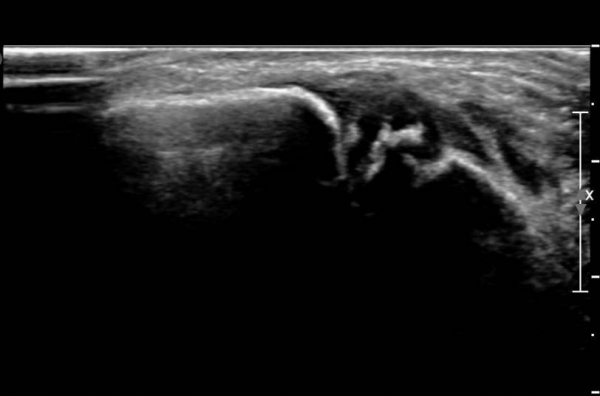

¾Õ°æ°ñºñ°ñÀδë Á¾´Ü¸é°Ë»ç¿¡¼­ °æ°ñºñ°ñÀδëÀÇ  Àú¿¡ÄÚ  ºÎÁ¾ ¹× ÀδëºÎÂøºÎ °æ°ñÀÇ

°ß¿­°ñÀýÀÌ  °üÂûµÊ(»çÁø 2, 3, 4)